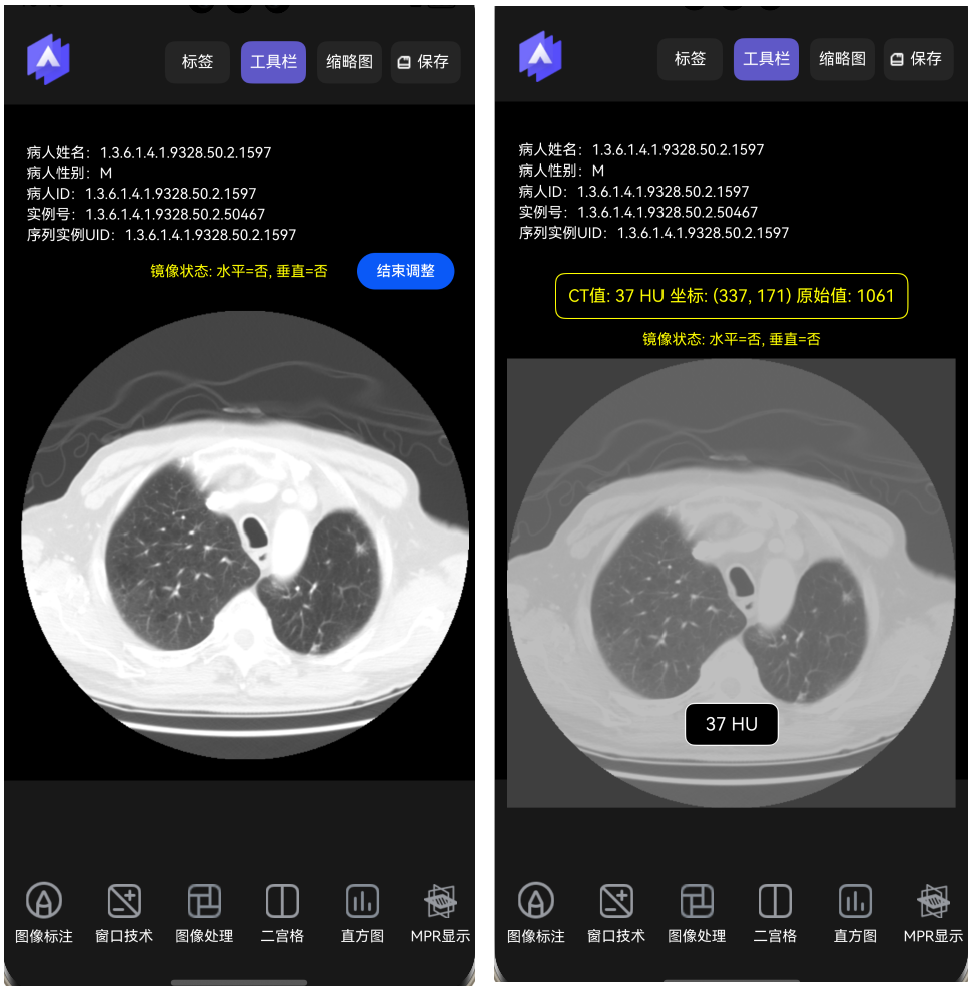

显示CT值。点击图像某个部位时在底部显示当前的CT值,如下图所示。